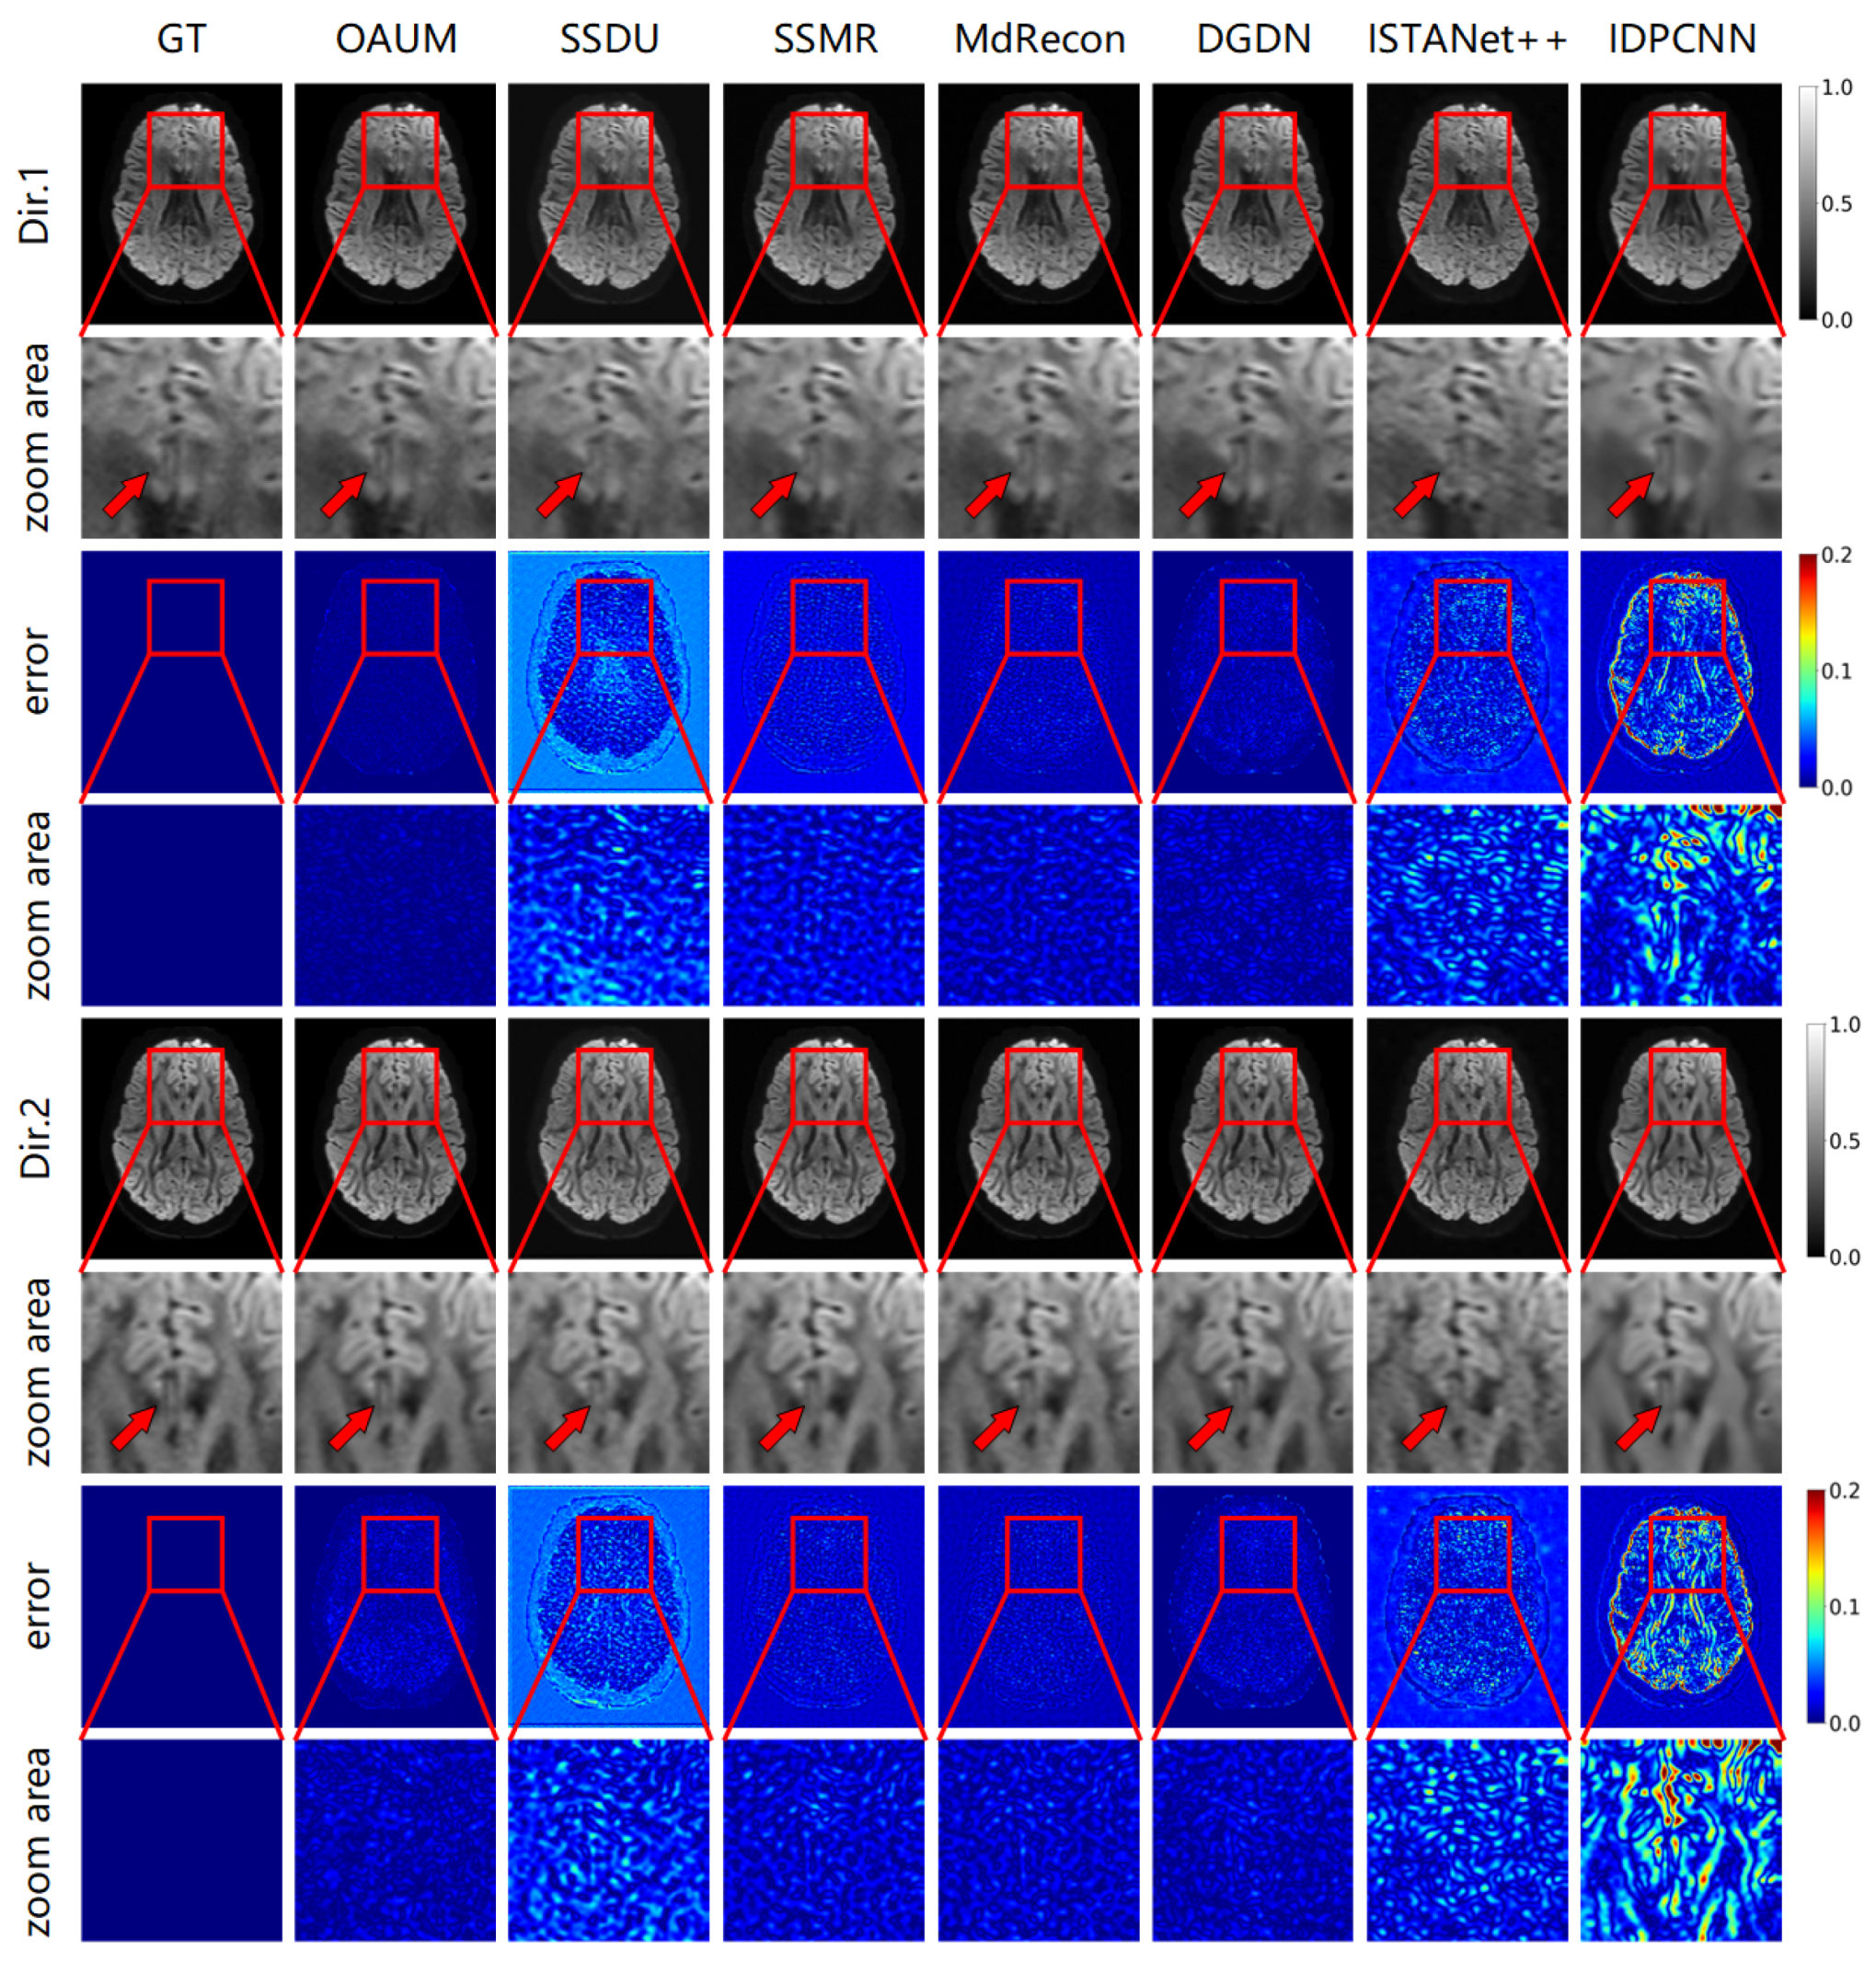

Figure 4 shows the DWIs reconstructed using the proposed model (OAUM) and various comparison models under 4-fold accelerated sampling, along with their respective ground truth (GT) images. For clarity, reconstruction results in two gradient directions are presented in Figure 4, and all results were normalized for consistency. Our method (OAUM) outperforms both self-supervised and supervised methods in terms of image quality improvement in both the gradient directions. Compared to the ground truth full-sampled data, OAUM has the smallest residual error when reconstructing DW images while exhibiting clearer details and textures that can be observed through red arrow areas. IDPCNN and ISTANet++ exhibit poor reconstruction performance at the brain structure edges, while SSDU performs poorly in background regions and skull edges. Although SSMR, MdRecon, and DGDN have acceptable residual ranges, their residual values are still larger than those of our proposed method when compared side-by-side.

Figure 5 demonstrates the reconstruction effect of our model at a higher sampling rate. The figure shows the reconstructed DWIs of each model and its residual images compared to the true fully sampled image at an 8-fold acceleration factor (sampling rate of 0.125). Our method outperformed all other methods in detail recovery, as shown by the red arrow in the DW image. Comparing the Dir.1 and Dir.2 directions, OAUM exhibited a worse performance in the Dir.2 gradient direction than the Dir.1 direction because Dir.2 DWIs were reconstructed from q-space undersampled data. However, compared to self-supervised method SSDU and supervised methods ISTANet++ and IDPCNN, OAUM still had significantly lower errors, demonstrating its superiority.

Figure 4. The DWIs reconstructed from models with acceleration factor (AF) = 4 and two diffusion gradient directions.

Figure 5. The DWI results reconstructed from models with acceleration factor (AF) = 8 and two diffusion gradient directions.